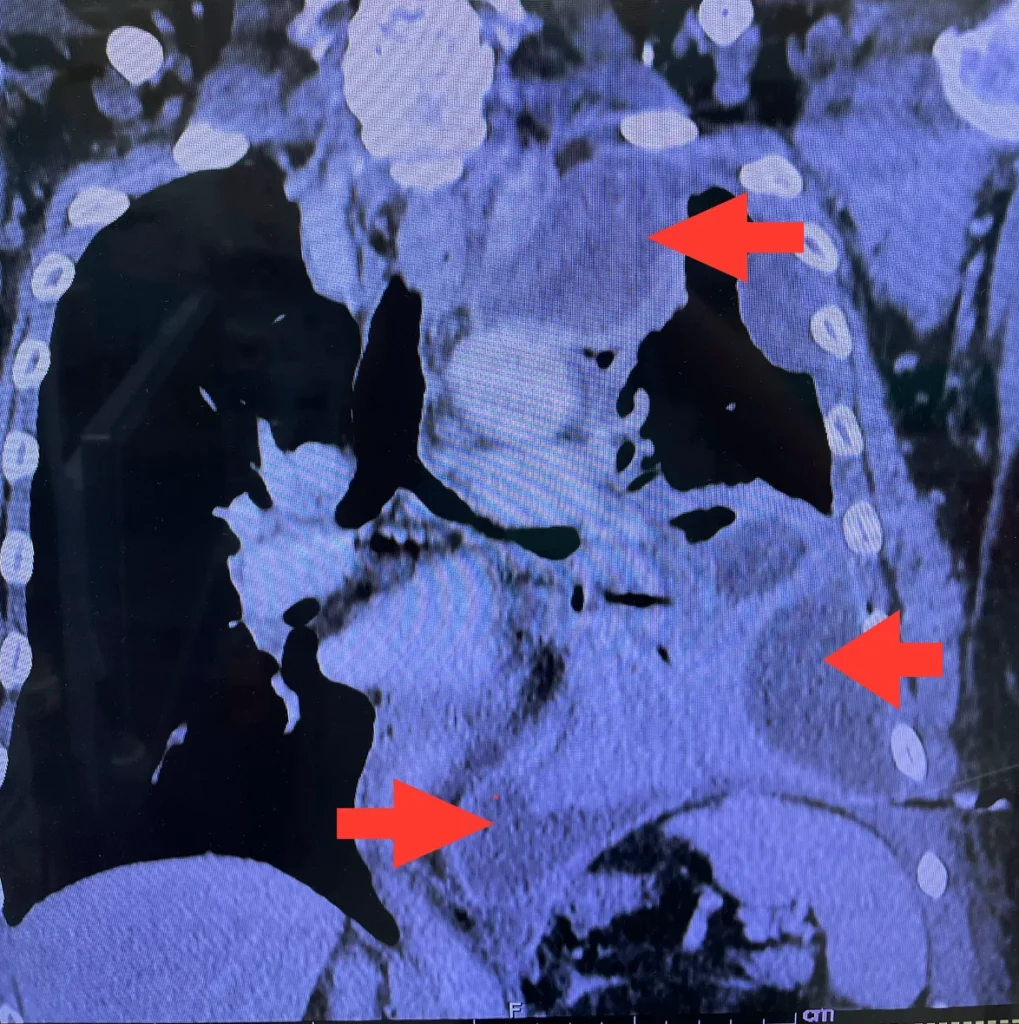

2. ระยะที่ 2 หรือ Fibrinopurulent phase พบในช่วงเวลา 1-6 สัปดาห์นับตั้งแต่เริ่มมีความผิดปกติ ซึ่งจะมีการกระตุ้นกลไกลการแข็งตัวของเลือด, การลดสลายของเส้นใยโปรตีนไฟบริน ทำให้มีเส้นใยโปรตีนสะสมมากขึ้น ลักษณะของเหลวจะเป็นหนองขุ่นข้นเหนียวหนืด เส้นใยโปรตีนปริมาณมาก ลักษณะเป็นน้ำหนองและเริ่มมีการสร้าง ปลอกแคปซูลรอบๆน้ำที่สะสม เปลือกของ capsule จะไม่หนามาก เยื่อหุ้มปอดทั้งชั้นนอกและชั้นในจะเริ่มหนาตัว เยื่อหุ้มปอดชั้นในจะเริ่มรัดปอดมากขึ้น ทำให้ปอดขยายตัวได้น้อยลงขณะหายใจของเหลวมักตรวจพบเชื้อแบคทีเรีย

3. ระยะที่ 3 หรือ Organizing phase พบในช่วงเวลา 5 สัปดาห์ขึ้นไปนับตั้งแต่เริ่มมีความผิดปกติ จะพบหนองเหนียวข้น ร่วมกับการหนาตัวของเยื่อหุ้มปอดมากขึ้น ระยะนี้ปอดจะถูกกดเบียดมาก และไม่ขยายตามการหายใจ หนองที่นำไปตรวจมักตรวจไม่พบ bacteria

- การตรวจภาพถ่ายรังสีทรวงอก (chest X-ray)